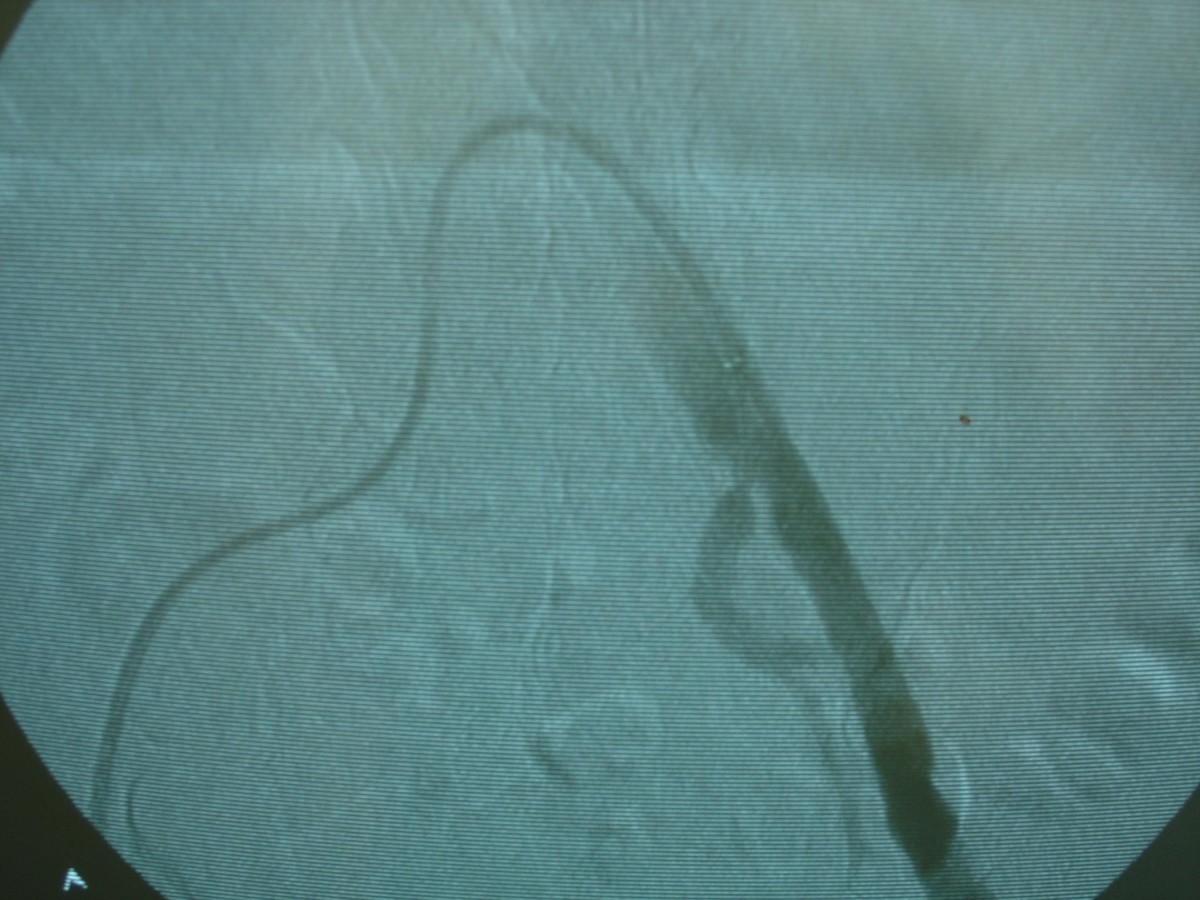

Ενδαγγειακή αποκατάσταση ανευρυσμάτων κοιλιακής αορτής

12ο Πανελλήνιο Συνέδριο Αγγειακής και Ενδαγγειακής Χειρουργικής

2010, Αθήνα